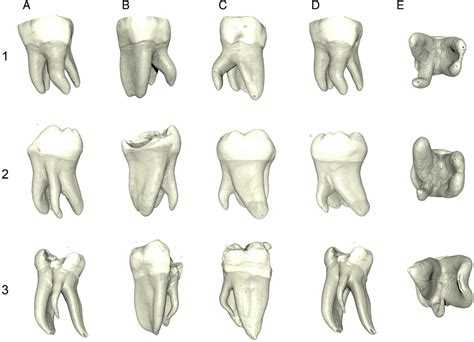

La anatomía de los conductos radiculares puede representar para los profesionales un complejo reto clínico que requiere habilidades diagnosticas, modificación de accesos, y pericia clínica para localizar, permeabilizar, desinfectar, y sellar con éxito el sistema de conductos radiculares. Este artículo discute las implicaciones clínicas del tratamiento endodóncico en primeros molares inferiores permanentes.

Las características anatómicas y la complejidad de los primeros molares superiores han sido ampliamente descritas en la literatura; sin embargo, el diente que se endodoncia con más frecuencia es el primer molar inferior. Su anatomía radicular y la configuración de sus conductos representan un importante reto, incluso para el endodoncista más experimentado. El tratamiento con éxito de los molares inferiores requiere un considerable conocimiento de la curvatura de los conductos y de las variaciones anatómicas.

Por otra parte, su forma irregular, las comunicaciones interconductos y las curvaturas no son visibles en las radiografías, lo que aumenta todavía más la dificultad del tratamiento. Se acepta de manera generalizada que no existe una técnica única para la limpieza y conformado de todos los casos. Por ello los endodoncistas deben ser capaces de entender completamente la morfología dentaria y la configuración de los conductos para así seleccionar la modalidad de tratamiento más adecuada para cada caso particular.

El número de raíces del primer molar inferior guarda relación directa con la etnia. La morfología de los conductos tiene efectos importantes sobre el protocolo de tratamiento. Las raíces mesiales presentan generalmente dos conductos, adoptando como configuraciones mas frecuentes la 2-2 y la 2-1. En un 2,6% de la población existe un tercer conducto. La configuración más frecuente en la raíz distal es la tipo I (62,7%), seguida de la tipo II (14,5%) y de la tipo IV (12,45%).

Basándose en todo lo anterior, nuestro grupo ha publicado recientemente una revisión sistemática de la anatomía radicular y de la configuración de los conductos del primer molar inferior permanente incluyendo 41 estudios con un total de 18.781 dientes25. De todos ellos, 2.450 (13%) eran molares que presentaban tres raíces. En un grupo de 4.745 molares, un 61,3% presentaban tres conductos, un 35,7% presentaban cuatro conductos, y un 0,8% cinco conductos.

De las 4.535 raíces mesiales, un 3,3% tenían un solo conducto, un 94,2% tenían dos conductos, y un 2,6% tres conductos. El treinta y cinco por ciento de las raíces mesiales presentaban una configuración de del sistema de conductos radiculares tipo II, un 52,3% una configuración tipo IV, y un 0,9% una configuración tipo VIII. De las raíces distales, el 62,7% presentaban una configuración tipo I, un 14,5% una configuración tipo II, y un 12,4% una configuración tipo IV.

Respecto al número de forámenes, en las raíces mesiales, el 38,2% presentaban un foramen, un 59,2% presentaban dos foraminas, y un 1,6% presentaban tres foraminas. En las raíces distales, el 77,2% presentaban un foramen, mientras que el 22,2% presentaban dos foraminas. En términos de istmos tipo V, el 54,8% de las raíces mesiales los presentaban en el tercio medio y tercio apical, mientras que el 20,2% de las raíces distales los presentaban en el tercio medio. Esta completa revisión nos aporta información directamente relacionada con nuestros procedimientos clínicos.